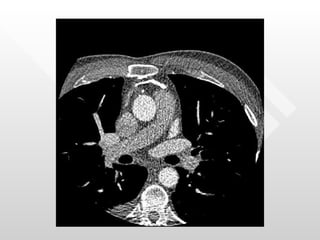

Normal pericardial thickness Multiple adhesions between the pericardium and the heart RV directly below the sternum

Normal pericardial thicknessMultiple adhesions between the pericardium and the heart RV directly below the sternum